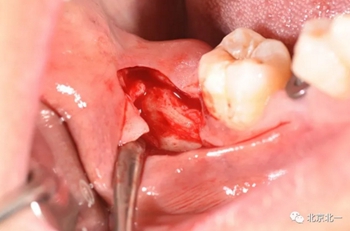

第二步:拔牙

切口設(shè)計關(guān)鍵點偏頰側(cè)。

去骨:原則暴露最大周徑線即可, 盡可能少去骨, 微創(chuàng)拔除。

截冠:有絲分裂至關(guān)重要。 保證微創(chuàng)下拔除智齒。

北一種植王明老師總結(jié):本病例難點在于設(shè)計多學(xué)科治療。 治療周期拉長, 患者智齒低位, 拔除困難, 容易造成神經(jīng)麻木。 必須由經(jīng)驗醫(yī)師主刀。 北一微創(chuàng)拔牙理念主張將牙齒進行有絲分裂, 進行智齒粉碎。 對工具要求較高。 較少患者痛苦。